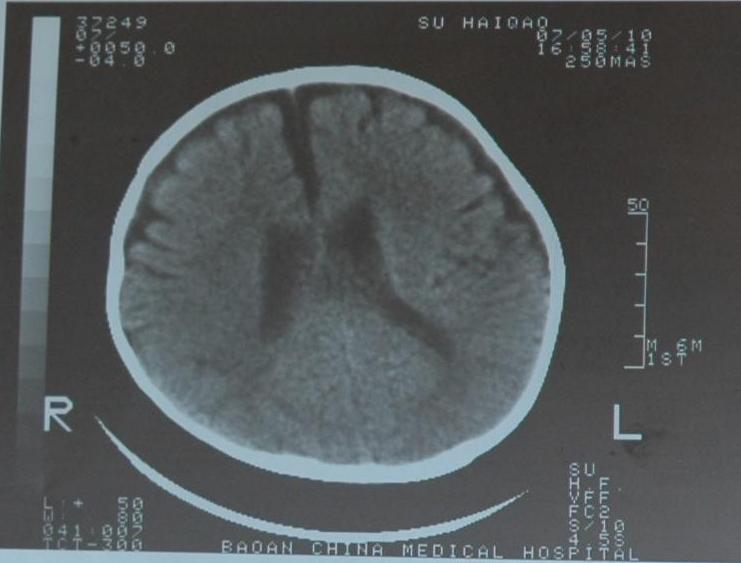

检查部位:头颅ct扫描

层厚:10mm     层距:10mm

扫描所见:双侧额颞部颅骨内板下方见对称性带状脑脊液样低密度影,并向前纵裂延伸,两侧大脑半球、脑干及小脑实质密度未见异常,侧脑室及三脑室略宽,双侧额叶脑沟深深加宽。四脑室形态无变形、移位或扩张,中线结构居中。

ct诊断:1、外部性脑积水(少量)。2、侧脑室、三脑室略宽,双侧额叶脑沟增深加宽,请结合临床。